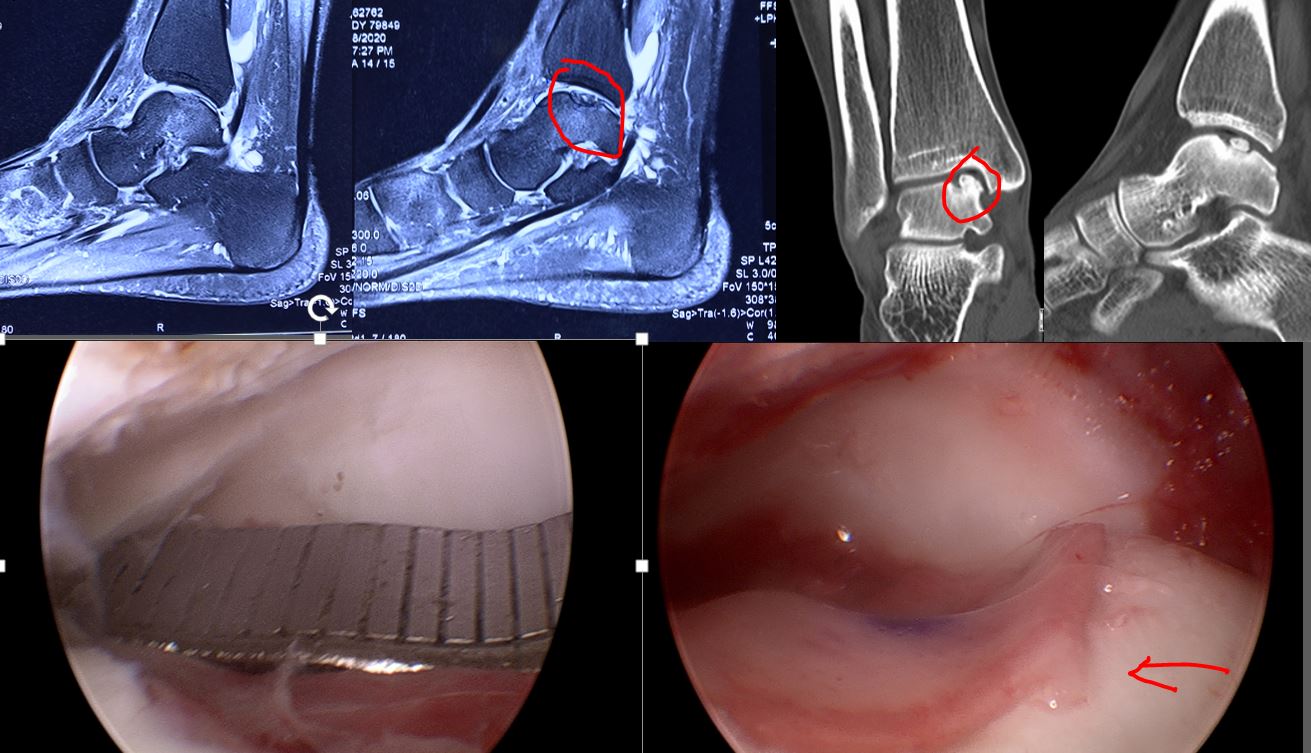

第一次手术,关节镜下软骨取样用于培养,同时去除增生的骨刺,清理关节的炎性滑膜、修复韧带操作等,创造良好关节关节微环境,利于软骨细胞移植修复。

(核磁上可以看见距骨软骨损伤)

第二次手术,关节镜微创MACI术(第一次手术2-3周进行),将培养的软骨细胞移植软骨损伤区域。